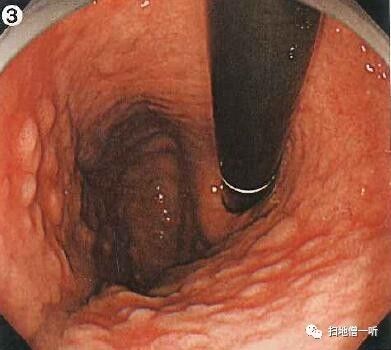

【8】

Q:胃癌在何处?

提示:请注意特殊胃癌

A:胃癌在图4及图5。HP未感染胃癌。

背景粘膜RAC阳性,提示HP未感染。穹隆部后壁可见一小片褪色粘膜,边界清晰,表面光滑,腺管扩张,伴随有蛇形血管。

靛胭脂染色后表面光滑,未见凸凹变化

NBI观察周围粘膜呈褐色改变,边界不甚清晰。

穹隆部后壁,O-IIb,6mm,胃底腺型胃癌,T1a (M),UL(-)

小结:

• HP未感染背景下注意观察胃底腺型胃癌

• 胃底腺性胃癌表现为平坦的褪色病变,表面扩张伴随蛇形血管

• 胃底腺性胃癌注意与MALT淋巴瘤及类癌相鉴别